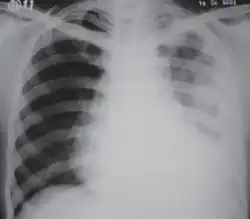

Fibrotórax extenso en el lado izquierdo. -

Radiografía de tórax que muestra opacidad heterogénea en la mitad izquierda del tórax por fibrotórax. -